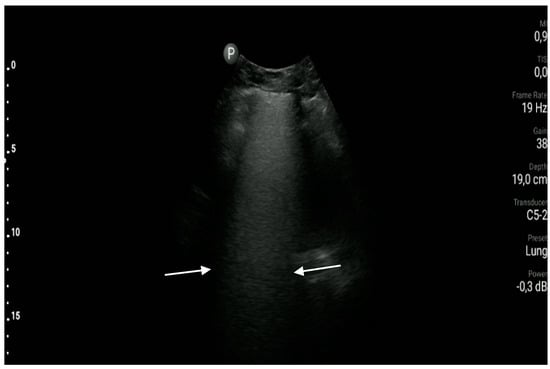

Atelectasis

- The sonographic features of compression atelectasis are as follows: pleural effusion, consolidation of a homogeneous echogenicity and echostructure, static air bronchogram, the air trapping sign, and normal vascular pattern in CD and PD options. (A1)

- The sonographic features of resorption atelectasis are as follows: consolidation of a homogeneous echogenicity and echostructure, fluid bronchogram, static air bronchogram, normal vascular pattern in CD and PD options, and possible visualization of a pathological mass at the top of the consolidation. (A1)

- (a)

- Blood flow in CD and PD options is normal only within the area of compression atelectasis, or within the consolidation area constituting resorption atelectasis and not being a pathological mass associated with cancer.

- (b)

- A static air bronchogram represents the presence of air in the bronchial tree and is visible during all respiration phases.